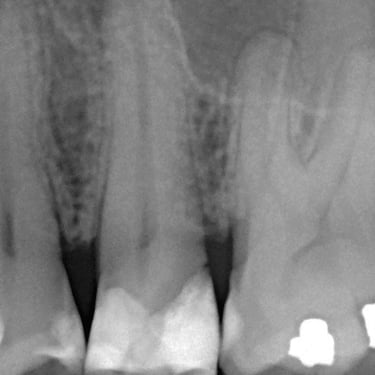

Lesión Endo-Perio Combinada

Una lesión endo-perio combinada es una condición en la que hay tanto una infección de la pulpa como una enfermedad periodontal.

Los pacientes pueden experimentar dolor, hinchazón y movilidad dental.

El tratamiento incluye tanto el tratamiento de conducto como el tratamiento periodontal para abordar ambas infecciones. La coordinación entre el endodoncista y el periodoncista es esencial.